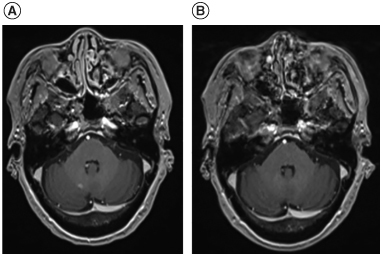

Background: Treatment for refractory or relapsed primary CNS lymphoma (r/r PCNSL) is challenging. Salvage whole-brain radiation therapy (WBRT) is an option but has a short duration of disease control, so additional treatment modalities are warranted. Case: A 75-year-old female with r/r PCNSL who had multiple progressions after multiple lines of treatment underwent salvage WBRT. The patient received ibrutinib, a Bruton's tyrosine kinase inhibitor, as maintenance therapy for 18 months following WBRT with the intention of increasing survival duration after salvage WBRT. She survived 81 months from diagnosis, including 57 months after completion of WBRT. Conclusion: This case presentation describes the experience of using ibrutinib as maintenance therapy in treating r/r PCNSL after salvage WBRT.

Abstract Image